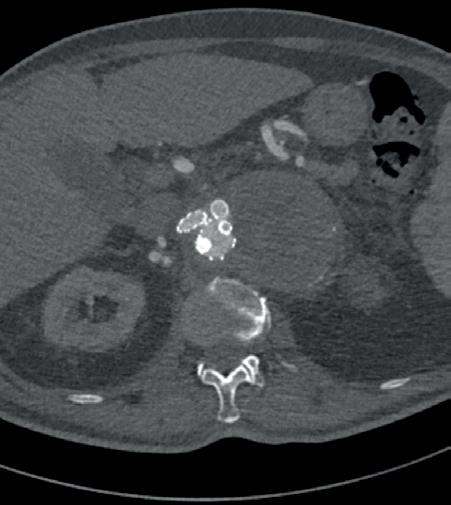

The Echocardiogram shows : LVSF was preserved without signs of pulmonary hypertension. AngioCT : AIA 72.4 x 57.3 mm in maximum diameter associated with a component of ulcerous and mural thrombus. (Fig. 1)